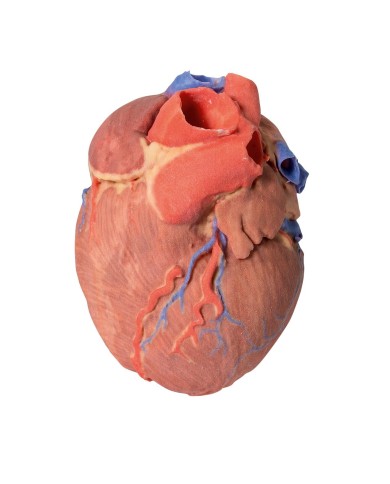

Realizzato in stampa 3D ad elevatissima risoluzione a colori.

Realizzato in stampa 3D ad elevatissima risoluzione a colori.

Realizzato in stampa 3D ad elevatissima risoluzione a colori.